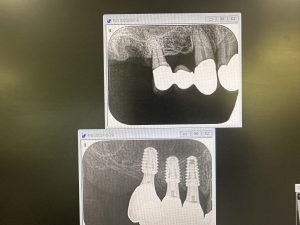

今年5月オペ、6番は残存骨2から3ミリ程度での、ソケットリフトデンサーバーによるリフト

4.5番は6wで仮歯装着、しかし6番は5ヶ月近くかかったが、本日最終補綴物セット

ジンジバルカウンツアー(擬似歯肉)、ペディフィケーションジグインデックス